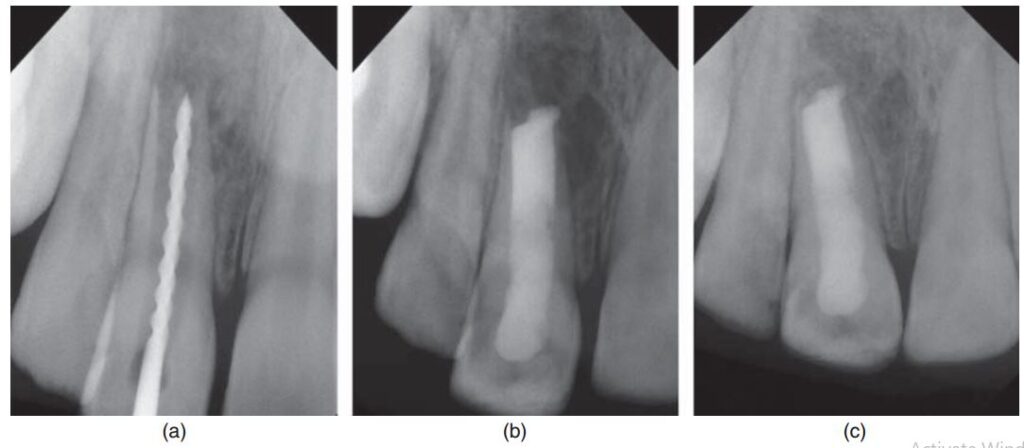

Hình 17.1. Chân răng cửa giữa hàm trên bên phải bị gãy sau khi điều trị đóng chóp thành công với canxi hydroxit và trám bít ống tủy bằng gutta percha. (a) Phim trước điều trị cho thấy lần điều trị trước kia với gutta percha ở răng cửa giữa trái không thành công. (b) Điều trị kích thích tạo chóp răng cửa giữa phải thành công. Răng cửa giữa trái được trám bít ống tủy bằng gutta percha và sau khi được cắt chóp.

Hình 17.1. (c) 18 tháng sau. Răng cửa phải được trám bằng gutta percha. Tổn thương quanh chóp răng cửa trái đang lành. (d) Gãy răng cửa giữa bên phải 3 tháng sau. Răng cửa trái tiếp tục lành thương bình thường.